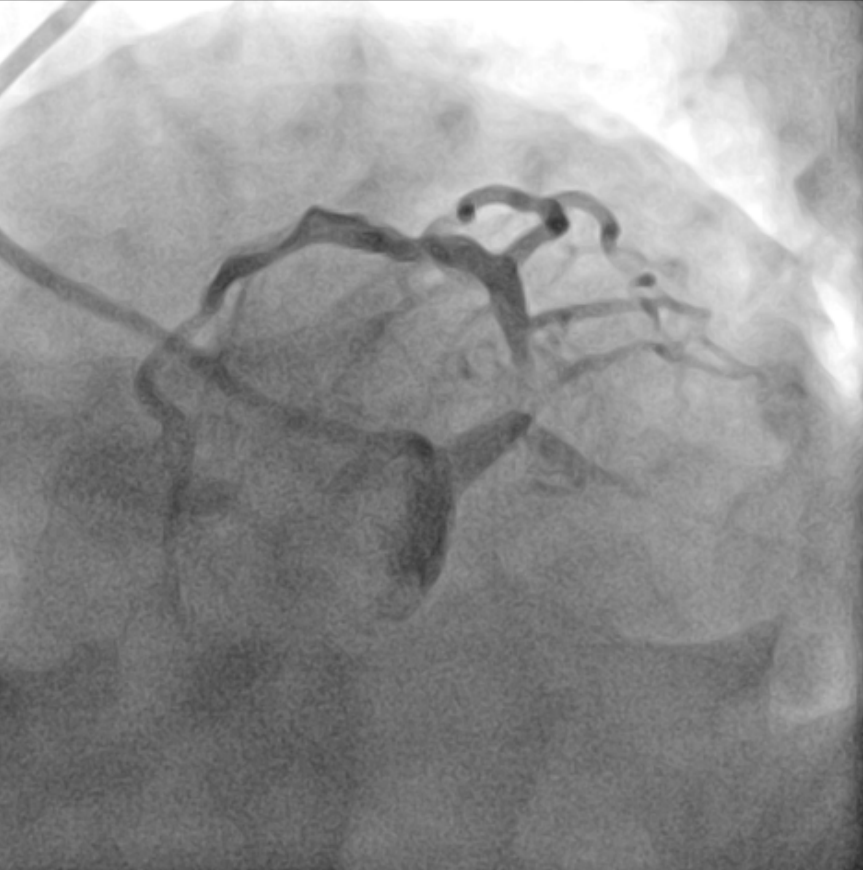

Coronary angiography revealed no specific findings in the right coronary artery, while showing collateral flow from the posterior descending artery to septal branches. Severe in-stent restenosis (ISR) was observed in the previous LM stent, accompanied by severe stenosis at the left circumflex (LCX) ostium resulting in TIMI flow grade 1.The procedure was performed via femoral approach using an 8 Fr sheath and Judkins 3.5 guiding catheter. Runthrough NS 0.014 wire was used for LAD wiring, which was successfully achieved. However, LCX wiring proved challenging and required a double lumen catheter (Asahi Sasuke 0.014, 3.2 Fr) for successful passage.Predilatation was performed using a semi-compliant balloon (Ryurei 2.0 ¡¿ 15 mm) for LCX and a non-compliant balloon (Selethru NC 3.5 ¡¿ 8 mm) for LM to LAD. Intravascular ultrasound (IVUS) evaluation was performed in both vessels to assess lesion characteristics. The treatment strategy involved drug-eluting balloon (DEB) therapy for LM-pLAD ISR and drug-eluting stent (DES) implantation in LCX with reverse crush technique.Additional lesion preparation was performed using a cutting balloon (Wolverine 3.5 ¡¿ 10 mm) for the LM-pLAD ISR lesion. A Xience 3.0 ¡¿ 15 mm stent was implanted in the proximal LCX. The LCX stent was then crushed using a non-compliant balloon (Selethru NC 3.5 ¡¿ 8 mm), followed by rewiring of LCX using the double lumen catheter and Fielder FC 0.014 wire.Kissing balloon dilatation was performed with non-compliant balloons (Selethru NC 3.5 ¡¿ 8 mm for LAD and 3.25 ¡¿ 15 mm for LCX) at 6 atm. Subsequently, drug-eluting balloon therapy (SeQuent Please Neo 3.5 ¡¿ 20 mm) was applied to the LM-pLAD ISR lesion, followed by final kissing balloon dilatation at 8 atm.Final IVUS evaluation confirmed optimal results in both LAD and LCX vessels. The procedure was completed without complications, demonstrating successful treatment of complex left main bifurcation disease with combined DEB and reverse crush stenting technique.